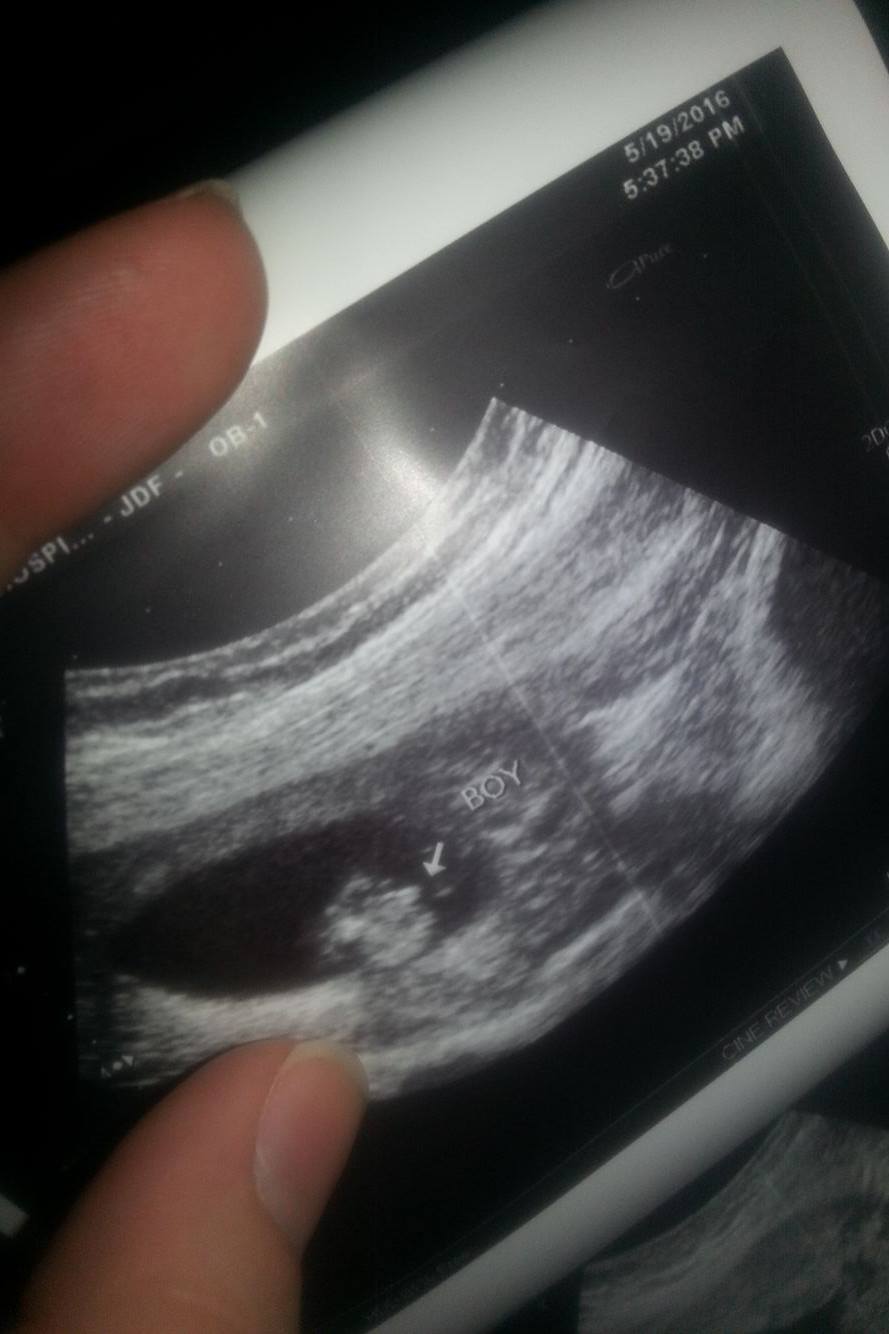

HELPPPP... Have been told: BOY (14wks), BOY (16wks), GIRL(17wks), & GIRL (18wks)

HELPPPP... Have been told: BOY (14wks), BOY (16wks), GIRL(17wks), & GIRL (18wks)!!

Absolutely completely confused & upset. A tech friend who works at our local hospital (so not an OB tech that views gender everyday, but does has experience & has been doing them for years) has been performing ultrasounds for me just out of excitement herself. I've so appreciated being able to watch my baby grow as I am high risk, & it keeps my mind at ease! BUT gender predictions have been a nightmare thus far. My latest just doesnt seem like normal "girl parts" to me. It is protruding far more than what I have seen on my two previous girls. The base of the the "three lines" isnt even attached at the bottom of the baby. Its odd to say the least. But some opinions will be greatly appreciated. My actual OB will be doing a gender u/s next week at 21 weeks so hopefully we will get some clarity. Regardless I feel like I will have a hard time trusting it & getting to bond with my SON or DAUGHTER :( ... hellllpAttachment 31823